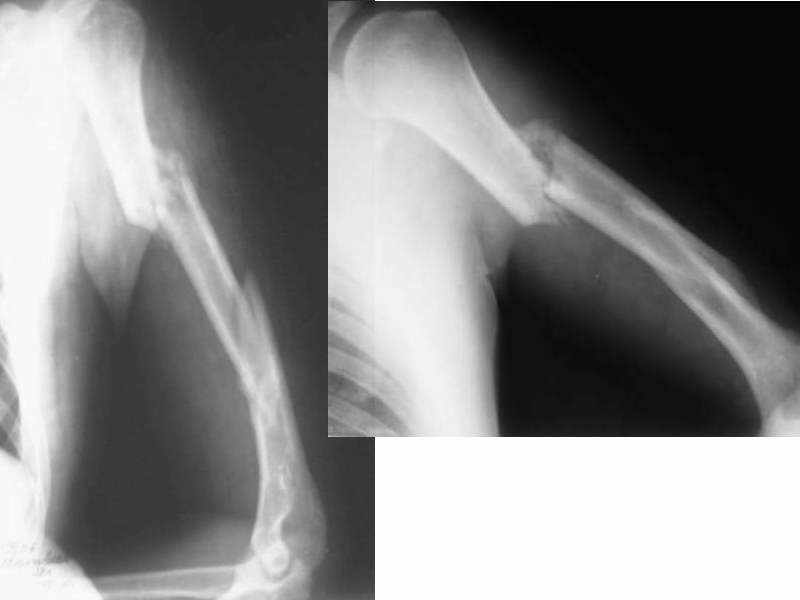

Двойной перелом плеча

Уважаемые коллеги! Больной 28 лет, по профессии монтажник. 30 августа получил изолированную травму: двойной перелом левого плеча(удар бетонной плитой) с парезом лучевого нерва.

Лечился в ЦРБ по месту жительства в травматологическом отделении - гипсовая лонгета по Турнеру. 6 октября попал в НИИТО. Выполнена <ревизия и невролиз лучевого нерва> - цитирую по выписке. Сначала планировался интрамедуллярный остеосинтез, но во время операции выявлена выраженная костная мозоль, остеосинтез не сделали. В настоящее время имеется вот такая картина (см. приложение). Локтевой сустав - контрактура под прямым углом, объем движений в пределах 5 градусов. Плечевой - движения по всем осям - до 45 гр. Лучезапястный - ладонное сгибание - 10 гр., тыльное - 5 гр. Парез лучевого нерва в течение всего времени - без динамики. Выраженный болевой синдром во всех суставах при попытке пассивных движений.

Поступил к нам в сломанной гипсовой лонгете (похоже ее не меняли за все время).Гипс сняли. Клинически - подвижности в зоне переломов и болей нет.

Какая тактика предпочтительна - оставить все как есть и заниматься устранением конрактур, или все-таки попытаться исправить ось плеча, заштифтовать и затем начать функциональное лечение?

Сейчас основная жалоба больного - это ограничение подвижности в суставах. А устранив деформацию в плече мы эти жалобы вряд ли устраним. Перелом плеча сросся, деформация до 20 градусов не несет никаких функциональных дефектов, так что лучше сосредоточиться на контрактурах.